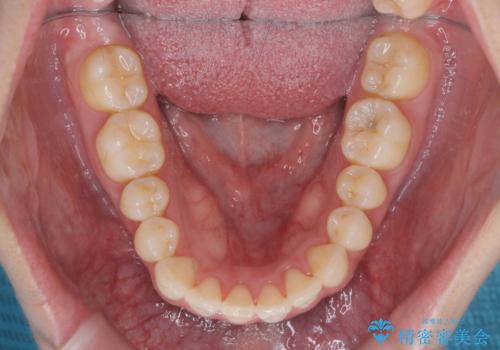

マウスピース 狭窄歯列の改善

- 噛み合わせが深い、笑った時の歯並びの改善を求めて来院されました。

マウスピース型の矯正装置インビザラインを用いた治療を計画します。

狭くなってしまった歯並びを放物線状に並べることで噛み合わせの安定・見た目の改善・ガタつきの改善を達成することができました。